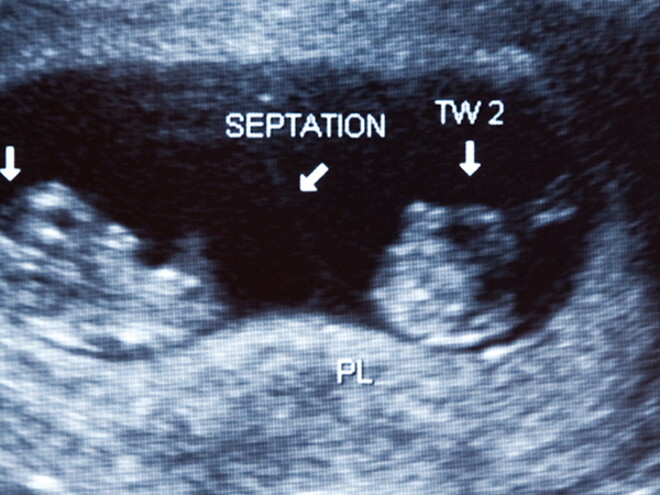

Multiple births

Regular prenatal care is most important if you are carrying more than one baby, as the risk to you and your babies is higher.